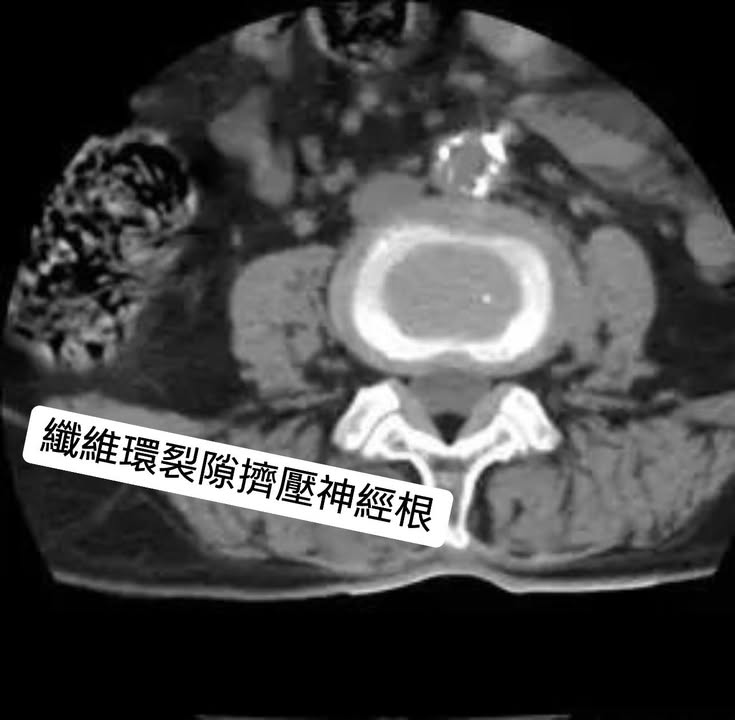

⭐️首先先說下椎間盤的結構,椎間盤位於兩個椎體之間用於承重和鏈接,主要有裡面的髓核和外面纖維環組成。這就是一個正常的腰椎間盤CT,可以看到椎間盤沒有變扁向周圍膨出或突出

⭐️ 當受到外力壓迫的時候,椎間盤就會變扁,這時髓核還在纖維環裡面,就好比一個豆沙包被壓扁了,豆沙餡還在包子里,椎間盤變扁就會向周圍膨出,壓迫後面的硬膜囊和後緣兩側的神經根,就會造成腰腿疼痛,感覺異常、麻木等,下面這個就是一個膨出的患者的CT表現。膨出一般可以休息、理療自行緩解。

3.纖維環輕微裂開